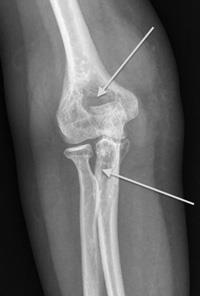

X-ray showing destruction of bone in an elbow with PVNS

This x-ray of an elbow with diffuse PVNS shows holes in the bone caused by the tumor.